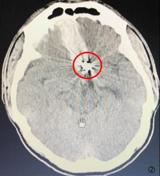

患者孙某,今年23岁,是个活泼开朗的阳光青年。三年前突发剧热头痛伴恶心呕吐急救至我们医院,查头部CT示“自发性蛛网膜下腔出血”,入院后查全脑血管造影DSA检查明确诊断为“前交通动脉瘤”,后因病情危急转至上海某三甲医院急诊行微创血管内弹簧圈栓塞术,术后恢复良好出院并叮嘱其3-6月左右需再次住院行全脑血管DSA检...2017-04-19